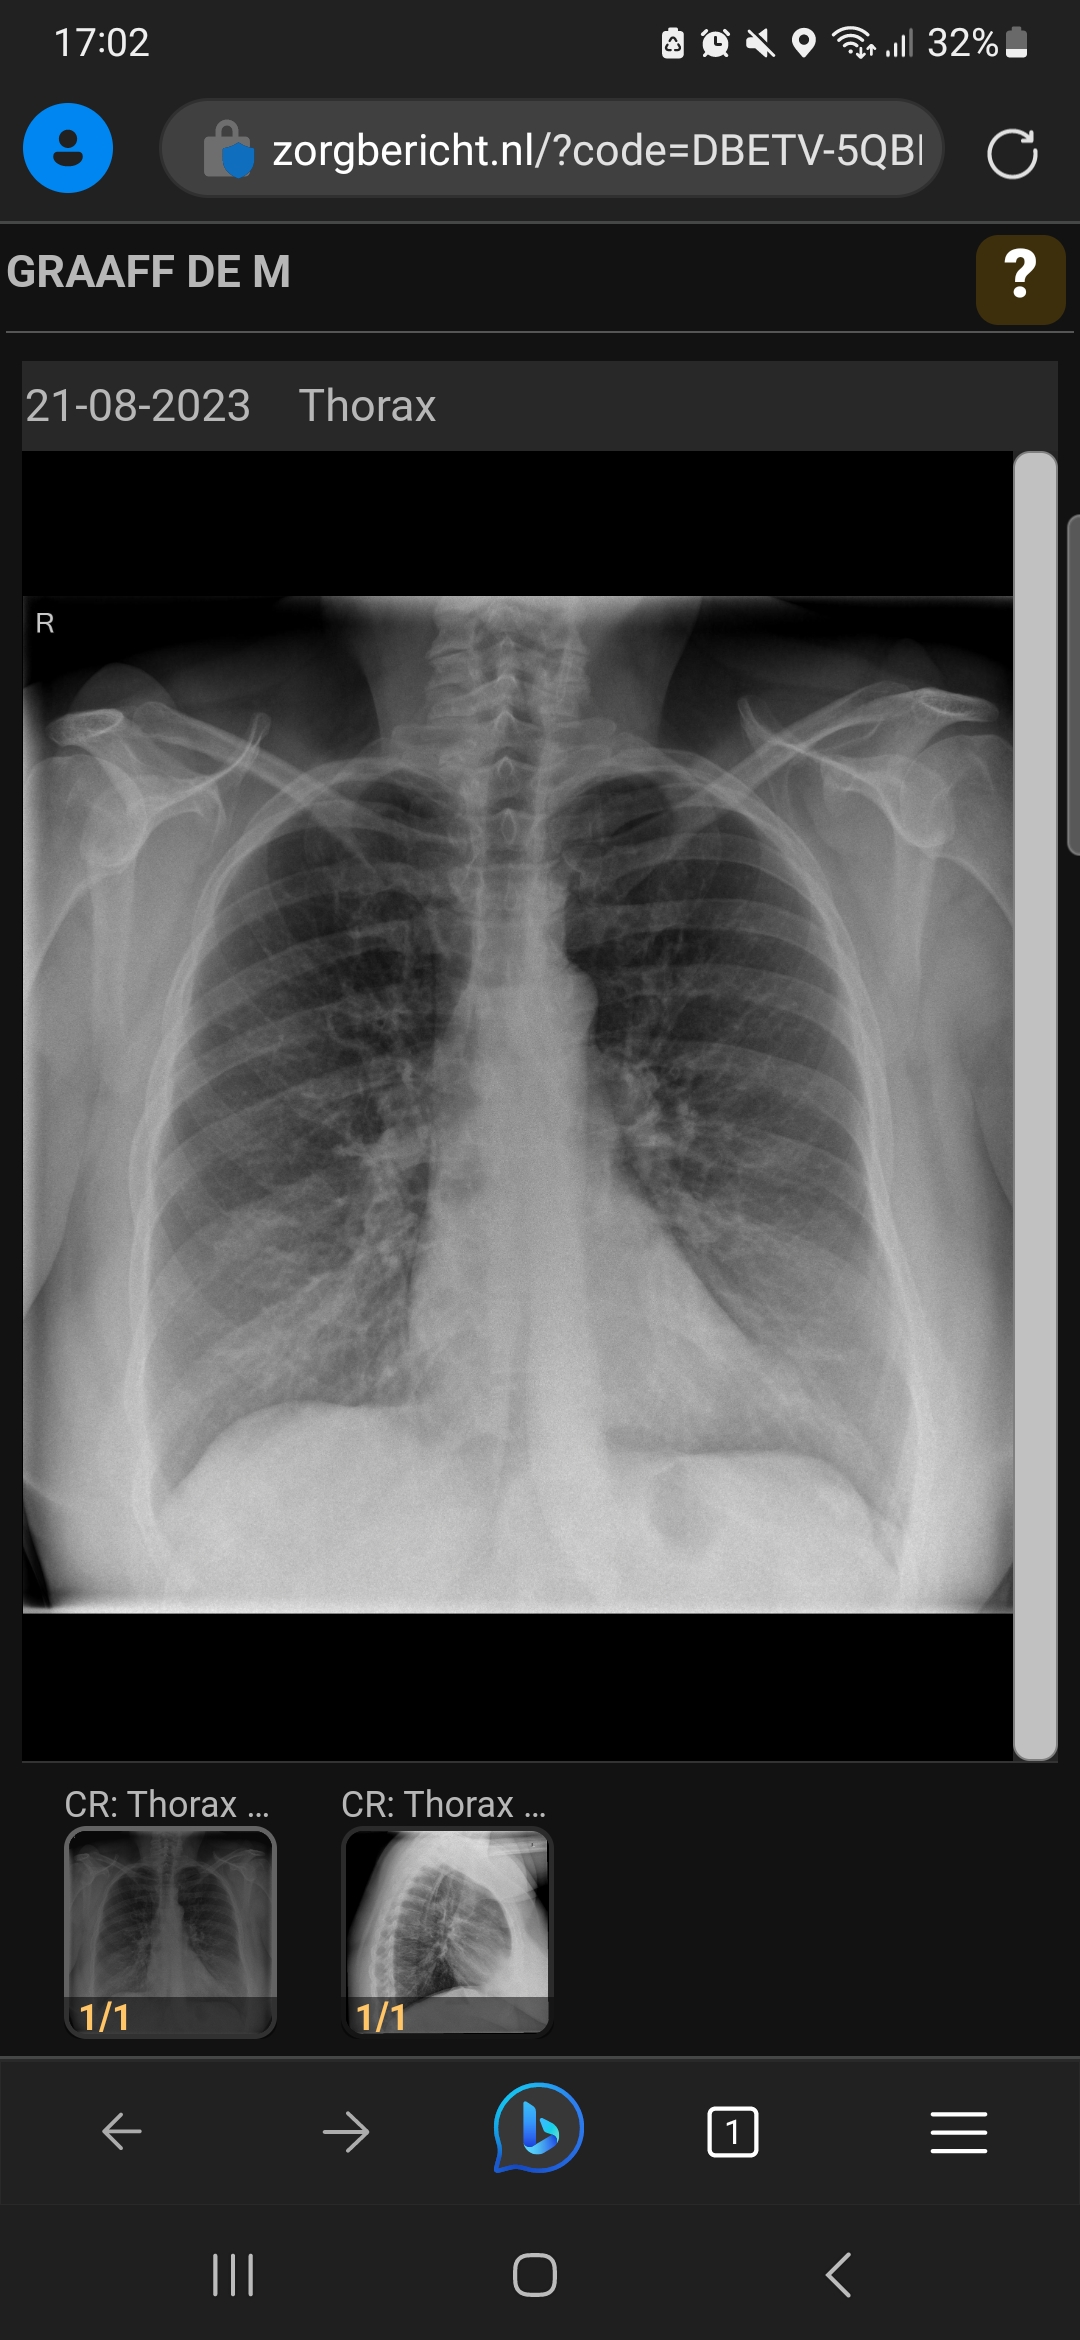

Versterkte tekening bibasaal, rechts meer dan links, DD infiltratief, advies controle na eventueel behandeling over 4-6 weken .

Versterkte tekening beiderzijds basaal kan te maken hebben met hartfalen, met een ziekte van het longweefsel zelf of soms een infectie. Soms is er een drogbeeld bij vrouwen door het borstweefel. Als ik de foto zie lijkt me er niets aan de hand, al kijk ik niet met hulp van een mooie radiologie monitor. Je eigen arts zal dit kunnen ophelderen tegen het licht van de reden waarom de foto is gemaakt